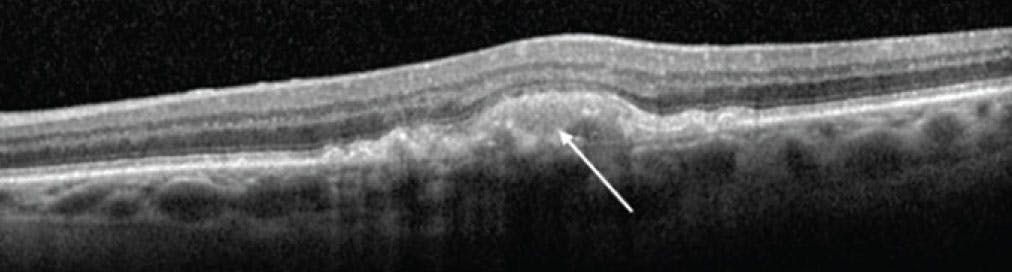

One study in the literature investigated nonexudative SRF in GA and observed a high percentage of progression to GA in areas of SRF overlying drusen and drusenoid pigment epithelial detachments.14 Our findings corroborate that these areas of nonexudative SRF likely represent a degenerative space beneath the retina, rather than an exudative fluid process, and are risk factors for progression to GA (Figure 1).13 SHRM/AVLs in the setting of dry AMD have more recently been hypothesized to represent an accumulation of various breakdown materials due to significant RPE stress and dysfunction or to act as a physical barrier for nutrient exchange, accelerating photoreceptor degeneration and GA progression (Figure 2).15,16

<p>Figure 1. The arrow points to nonexudative SRF with overlying ellipsoid zone attenuation that later progressed to GA.</p>

Figure 1. The arrow points to nonexudative SRF with overlying ellipsoid zone attenuation that later progressed to GA.